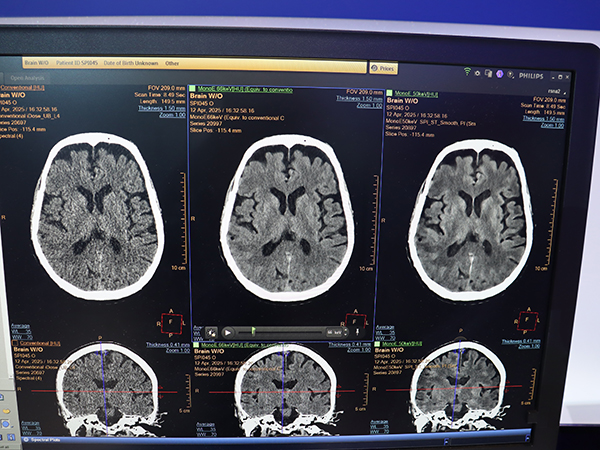

腹部や心臓,頭部など全身領域で使用でき,1mmスライス厚でもノイズの少ない高画質撮影が可能となっている。さらに,仮想単色X線(MonoE)による低エネルギー画像を併用することで,頭部では白質と灰白質のコントラスト向上,腹部では膵がんの境界の明瞭化や血管の視認性向上などが期待できる。AI画像再構成技術はプレミアムCT装置「CT 5300」から継承しており,10年に及ぶ2層検出器CTの集大成として大きくアピールした。

AI画像再構成「Spectral Precise Image」とMonoEで白質と灰白質のコントラストが向上(左:iDose4,中央:Spectral Precise Image・MonoE 66keV,右:Spectral Precise Image・MonoE 50keV)